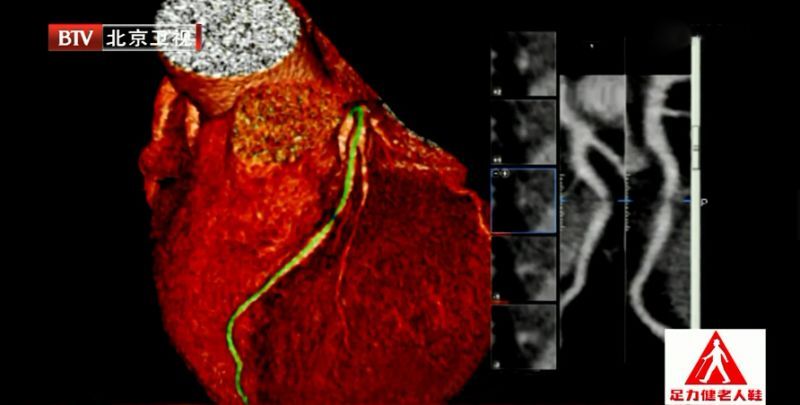

冠脉CT检查,揪出“坏”胆固醇

临床上,如果医生觉得这个患者需要做影像学检查来明确血管是否有病变的,在医院门诊可以做一个冠状动脉CT检查(加强CT)。冠状动脉CT检查需要打含碘的造影剂,红色血管在打完造影剂后就会显影,拍出胶片就能看到血管。

【专家提示】超声看不到细小的血脂,只有冠状动脉CT检查可以看得最清楚。这项检查要吃放射线,而且打的含碘的造影剂可能有过敏反应,需不需要做这项检查医生会为您评估,请遵医嘱。